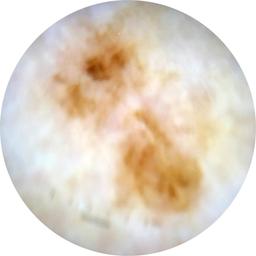

MEL-SELF - Dermoscopic

- Name: MEL-SELF - Dermoscopic

Description:

Dermoscopic lesion images (close-up views of benign and malignant lesions) from the MEL-SELF trial (the Melanoma Self Surveillance trial).